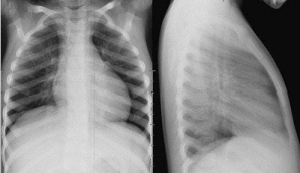

Phát hiện bệnh lý phổi phổ biến: Viêm phổi, lao phổi, tràn dịch màng phổi, u phổi, giãn phế nang, xơ phổi, khí phế thũng, COPD (bệnh phổi tắc nghẽn mạn tính)…

Hình ảnh rõ nét, độ phân giải cao: Cho phép quan sát chi tiết tổn thương nhu mô phổi, các vùng mờ, tổn thương dạng nốt, hang lao…